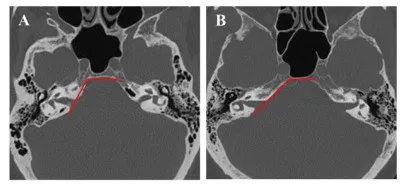

图7. 岩斜角与上半规管突起的变异。轴位CT扫描呈现两种不同的岩斜交界。岩骨与斜坡之间的夹角可在较小(123°,A)到较大钝角(142°,B)之间广泛变化。